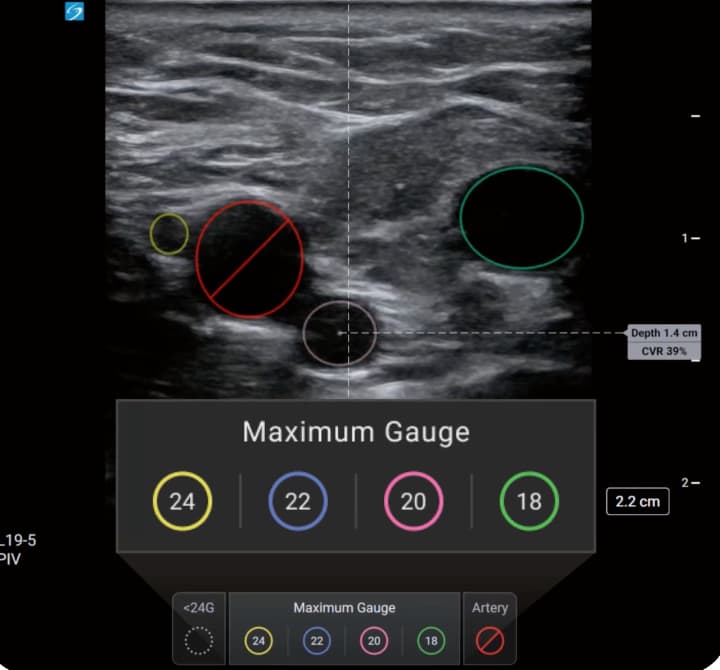

The AI-driven tool aims to assist healthcare professionals by identifying candidate veins and assessing vessel size during pre-procedural scanning. PIV Assist provides real-time differentiation between veins and arteries whilst calculating the catheter-to-vein ratio (CVR) to recommend maximum cannula sizes.

The system employs colour-coded visual guidance to assist procedural planning. Veins are marked according to maximum recommended catheter gauge, whilst arteries appear highlighted in red. The feature displays CVR calculations in real-time and indicates the depth to the centre of each identified vessel.